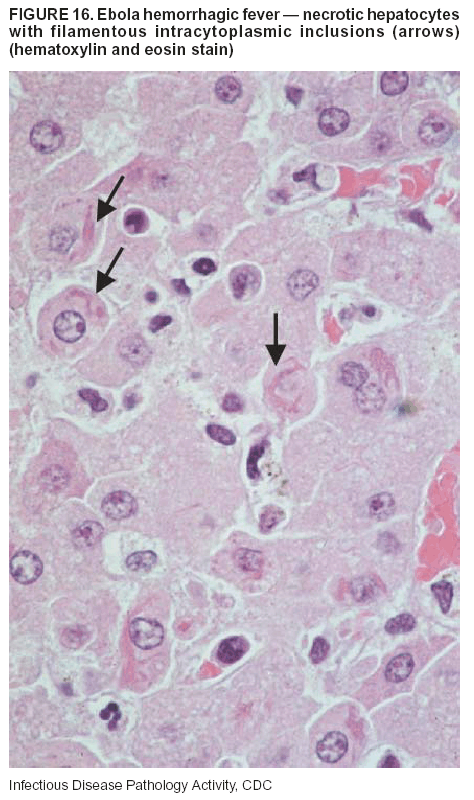

Pathologic Findings. The term viral hemorrhagic fever is reserved for febrile illnesses associated with abnormal vascular regulation and vascular damage. Common pathologic findings at autopsy include petechial hemorrhages and ecchymoses of skin (Figure 15), mucous membranes, and internal organs. Although systemic hemorrhages occur in the majority of viral hemorrhagic fevers, certain agents infect specific cells and thus histopathologic features can differ among agents. Necrosis of liver and lymphoid tissues, as well as diffuse alveolar damage, occur in the majority of viral hemorrhagic fevers, but can be more prominent for certain infections (e.g., midzonal hepatocellular necrosis is prominent in yellow fever, but not in dengue). Viral inclusions can be visualized in hepatocytes with Ebola or Marburg infections by using light and electron microscopy (Figure 16) (49--54).